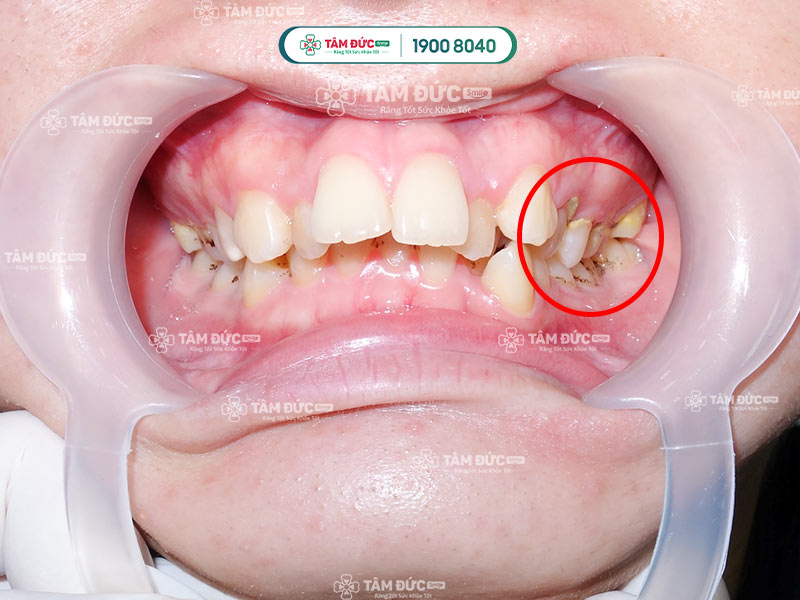

Cận cảnh cạo vôi răng cho khách hàng 35 năm chưa từng cạo vôi răng.

Cao răng làm hỏng răng nhanh chóng